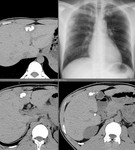

[画像診断]肝結核について 2010-06-07

[画像診断]肝結核について